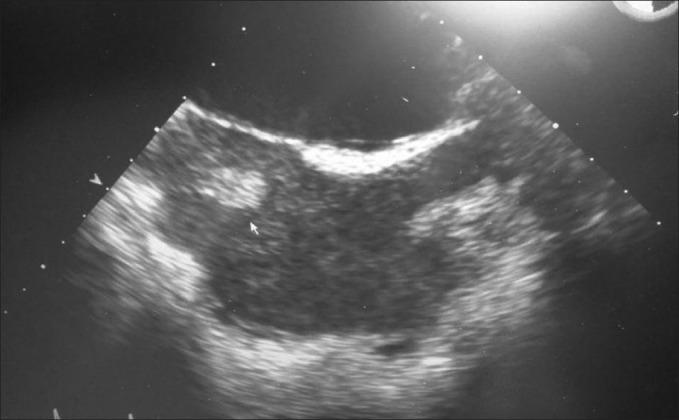

Patent foramen ovale (PFO) is defined as a valve-like opening at the level of foramen ovale or between septum primum and secundum without evidence of the anatomical defect. Paradoxical embolism (PDE) is an embolus passing through a defect PFO leading to end-organ dysfunction. PDE in septic shock is not yet reported in the literature. A 49-year male presented to the emergency department with shortness of breath since one day and pain in the left side of the chest. Chest x0 -ray revealed middle-left lobe pneumonia with pleural effusion; he was started on Co-amoxiclav, and admitted to the ward. After 6 h, his chest pain suddenly significantly increased difficulty in breathing and his oxygen saturation dropped. X-ray of the chest showed left pneumothorax, chest drain was inserted and he was intubated. He became hemodynamically unstable with maximum ventilatory support and noradrenalin. On day 4, he was found to have new pansystolic murmur in the tricuspid area. An echocardiogram revealed global hypokinesia, two mobile thrombi in the right atrial cavity, and PFO. It was noticed that his right toe had blackish discoloration. An angiogram showed occlusion of the right superficial femoral artery and immediately an embolectomy. On day 11, he was transferred to the ward. PDE needs a high index of suspicion in septic shock patients with ARDS. PDE requires PEEP adjustment, early anticoagulation, and thromboprophylaxis.

卵圆孔未闭(PFO)被定义为在卵圆孔水平或原发隔与继发隔之间的类似瓣膜的开口,且无解剖学缺陷的证据。反常栓塞(PDE)是指栓子通过卵圆孔未闭缺损导致终末器官功能障碍。脓毒性休克中的反常栓塞在文献中尚未见报道。一名49岁男性因一天来呼吸急促和左侧胸痛就诊于急诊科。胸部X线显示左中叶肺炎伴胸腔积液;给他使用了阿莫西林克拉维酸钾,并收住病房。6小时后,他的胸痛突然明显加重,呼吸困难,血氧饱和度下降。胸部X线显示左侧气胸,插入胸腔引流管并对他进行了气管插管。在最大通气支持和使用去甲肾上腺素的情况下,他的血流动力学仍不稳定。在第4天,发现他在三尖瓣区有新出现的全收缩期杂音。超声心动图显示整体运动减弱、右心房腔内有两个活动血栓以及卵圆孔未闭。注意到他的右脚趾有发黑变色。血管造影显示右股浅动脉闭塞,随即进行了栓子切除术。在第11天,他被转入病房。对于患有急性呼吸窘迫综合征的脓毒性休克患者,需要高度怀疑反常栓塞。反常栓塞需要调整呼气末正压、早期抗凝和血栓预防。